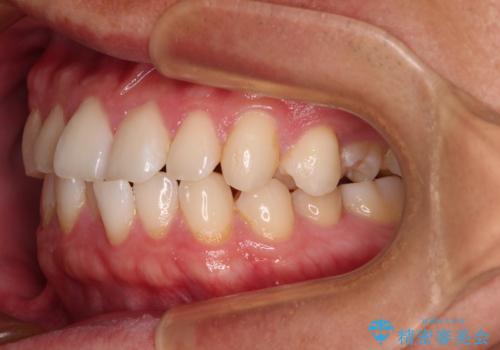

前歯のガタガタ・奥歯のかみ合わせ(シザーズバイト)を改善|1年半で完了したメタルブラケット矯正

今回ご紹介するのは、「前歯のガタガタ(叢生)」と「奥歯のかみ合わせ(シザーズバイト)」にお悩みでご来院された患者様の症例です。

▼ 診断

・上顎左右の第二大臼歯が頬側へ転移し、シザーズバイト(scissors bite)の状態

・上顎左側第二小臼歯が90度捻転しており、噛み合わせに影響